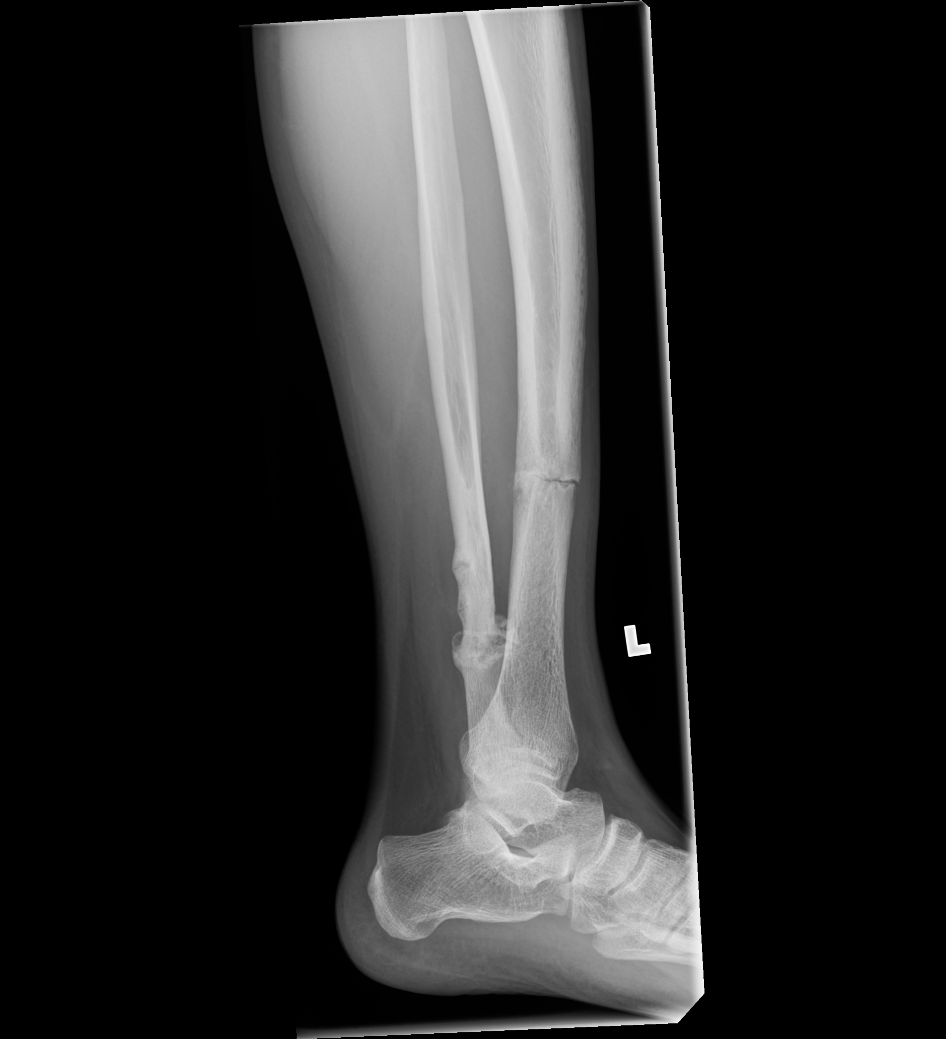

From eorif.com

Tibial Shaft Stress Fracture Images eORIF Stress Fracture Tibia Not Healing The vast majority of stress fractures will heal if treated correctly and promptly. Stress fractures take longer to heal and may require a brace, a walking boot, and crutches. Often you then see new bone growth where it has begun to heal. Learn how to prevent and treat them. Stress fractures are tiny cracks in bones often caused by overuse. Stress Fracture Tibia Not Healing.